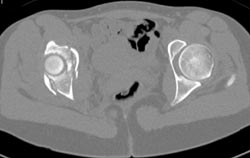

Cystic Changes in Left Acetabulum